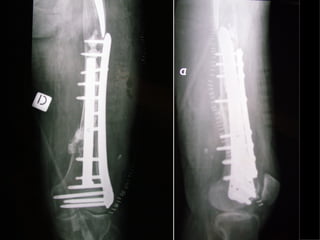

INDICAZIONI COMUNI Fratture sovracondiloidee Fratture intercondiliodee Fratture diafisarie distali PARTICOLARI Fratture con grave osteoporosi Fratture periprotesiche

VANTAGGI CHIRURGIA MININVASIVA Mini Open Inserimento della placca sottocutaneo per scivolamento Viti percutanee Preservazione dei tessuti molli Ridotto danno vascolare Rapida ripresa funzionale

F, 68 y